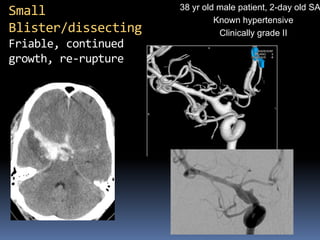

38 yr old male patient, 2-day old SAH

Known hypertensive

Clinically grade II

Small Blister/dissecting Friable, continued growth, re-rupture

38 yr oldmale patient, 2-day old SAH Known hypertensive Clinically grade II Small Blister/dissecting Friable, continued growth, re-rupture